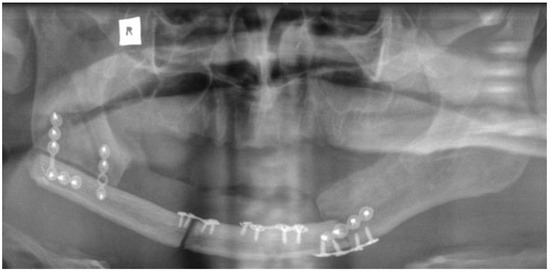

The mandibular resection is performed utilizing a horizontal osteotomy (Figure 1) above the mandibular angle on one side and a stepped body or angle osteotomy on the other side (Figure 2). A silicone template is created to the shape and dimension of the resected mandibular segment. The template is used as a guide to osteotomize the fibula at the donor site to reproduce the middle symphyseal segment of the mandible without shortening the fibula. The flap is then transferred to the recipient site and oriented so that one end will fit in the stepped osteotomy in a key and lock fashion (Figure 3) and the other end of the flap will overlap with the horizontal mandibular osteotomy (Figure 4), allowing room for adjustment in the anterior posterior direction to achieve the desired chin point projection (Figure 5). When the desired projection is achieved—guided by the silicone template—both ends of the flap are marked with a sterile pencil and trimmed using the saw; then miniplates are used to fix the flap in place (Figure 6).

Our technique is unique as it allows flexibility in adjusting the chin point projection to give the best possible aesthetic outcome. Trimming of the flap ends is performed at the recipient site to reduce the risk of short flap, but should this happen, the overlap at the horizontal osteotomy side will allow for compensation (Figure 4). Moreover, the greater surface contact area at the horizontal osteotomy side together with the key and lock fitting at the stepped osteotomy side (Figure 3) increase the stability of the flap and reduce the risk of rotation, hence allowing the use of miniplates for fixation; this in return allows room for placing more than one plate on each side, adding to the stability. The use of miniplates for fixation also facilitates the placement of implants in future rehabilitation.

Figure 6. An orthopantomogram showing the fibula flap in place with the horizontal and stepped osteotomy technique.